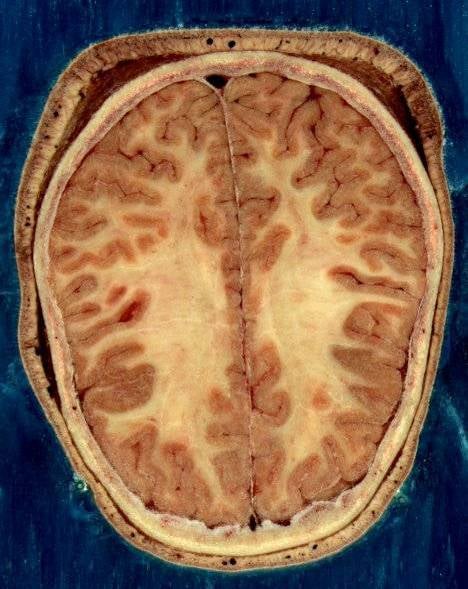

A mozgásfolyamatokat a központi idegrendszer szabályozza. A parancsimpulzusok az agykéreg idegsejtjeitől induló és a gerincvelőben folytatódó idegpályákon keresztül jutnak a mozgatóizmokhoz. Az idegpályák két részre oszthatók: Piramis-pályarendszer idegsejtjei az agykéregben találhatók. Hosszú rostjai kisujjnyi vastag kötegekbe szedődve haladnak a gerincvelőben.A gerincvelői pályarendszer gerincvelőben induló sejtjeinek rostjai kötegekben haladnak a gerincvelőben. A gerincvelői pályarendszer átveszi a piramispálya által közvetített impulzusokat és továbbítja az izomzathoz.Myatrophiás lateralsclerosis esetén a gerincvelő oldalsó pályája, a plexus lateralis, a piramispálya, a gerincvelői pályarendszer, a perifériás mozgatóidegek egyaránt károsodnak. A folyamat következtében bénulás, majd izomsorvadás alakul ki.Myatrophiás lateralsclerosisban a szintén idegeket, idegrostokat károsító sclerosis multiplexszel ellentétben érzészavar nem lép fel.A myatrophiás lateralsclerosis igen súlyos, feltartóztathatatlanul súlyosbodó, jelenlegi tudásunk szerint gyógyíthatatlan betegség. A betegek 80 százaléka a tünetek jelentkezését követő első három év során meghal. Az egyre fokozódó is kiterjedő bénulás a légzőizomzatot is károsítja. Ennek következtében a beteg légzése lényegesen megnehezül. A garatizmok bénulása táplálkozási elégtelenséget okoz. A garatreflexek károsodása miatt a beteg aspirál, ennek következtében tüdőgyulladás lép fel.Egyes esetekben a bénulás csupán bizonyos perifériás izmokat érint, a többi izomzatra nem terjed tovább.